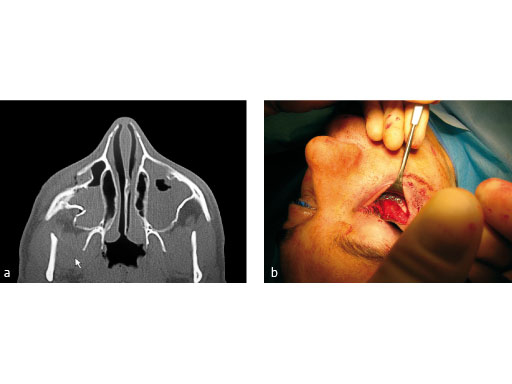

Fig 1ab

Treatment of zygomatic fracture with matrix midface plates.

Case images courtesy of Scott P Bartlett, Philadelphia, US